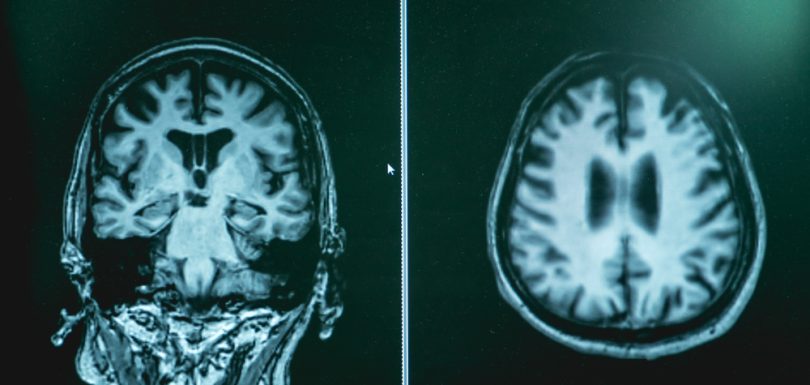

How Alzheimer’s Diagnostic Testing and Early Detection in Hagerstown, Maryland Strengthens Families

It’s never easy to make sense of changes in memory or behavior, but getting answers from experts sooner rather than later makes everything feel a bit less overwhelming.